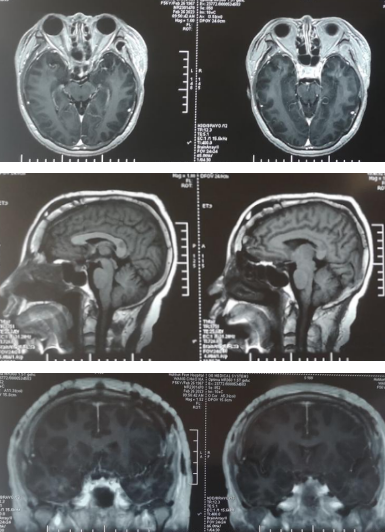

术后复查:头颅核磁

手术过程:麻醉医生贺林春精心细致地为患者实施气管插管全麻,BIS和鼻温监测,以及中心静脉置管,为手术提供安全保障;在贾群英护士长,手术护士乌日罕、樊荣的默契配合下,手术顺利进行,术中见肿瘤基地位于鞍结节,前方向蝶骨平台区生长,两侧包绕颈内动脉及双侧视神经,并向视神经管内生长,后方压迫垂体及垂体柄,向上向后推挤视交叉及三脑室底部,肿瘤色粉红,质地软韧,血供丰富,与视神经粘连严重,显微镜下分块切除肿瘤。术后病理回报砂粒体型脑膜瘤(WHO I)。术后患者视力、视野明显好转,复查头颅核磁肿瘤切除干净。